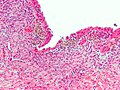

Criteria - need at least 2 / 3 for the diagnosis:[13]

- Endometrial glands - endometrial glands are classically: circular, with nuclei that are hyperchromatic & cigar-shaped.

- Endometrial stroma - endometrial stroma is classically: cellular and hyperchromatic (may resemble a lymphocytic infiltration on low power).

- Hemosiderin-laden macrophages - light brown, may be granular.

Notes:

- The epithelial component (1) may appear cuboidal in cysts or be sloughed-off, i.e. absent.

- The microscopic correlation of chocolate cyst is: light brown acellular material; this can be considered as a substitute for (3) - hemosiderin-laden macrophages.

- Epithelial component may have tubal metaplasia.[14]

- Endometriosis may mimic cancer[15] - see images below.

- If it is just endometrial type glands - the stroma is missing... it is probably endosalpingiosis.